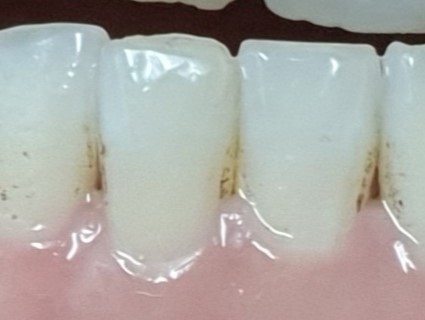

Black stain

특히 블랙스테인의 경우 한번 발생하면 잘 없어지지가 않습니다.

보통 소아에서 생기며 시간이 지나면 스스로 없어지는 경우가 많은데

성인이 되어서 생기는 분들이 있습니다.

블랙스테인의 원인은 Actinomyces 속 세균들 때문인데 이 세균들이

입속의 물질들과 반응해서 황화물이나 금속 이온으로 치아에

착색을 시키는데 정확한 원인은 아직 밝혀지지 않았습니다.

충치로 오해를 할 수도 있지만 블랙스테인이 생기면 오히려 충치가 덜 생깁니다.

누구에게나 흔하지는 않은데 한번 생기기 시작하면 스케일링을 해도

얼마 지나지 않아 바로 다시 생기고 무엇보다 미관상 보기 좋지 않아서

그로 인해 대인관계를 기피하게 되고 어려워지는 스트레스를 받게 됩니다.

제거를 위해서 분노의 양치질을 하다간 잇몸이 망가지는 걸 경험하게 됩니다.